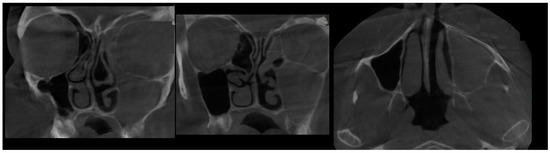

- Type 1 SSS (pure SSS = pSSS) (Figure 2) MS four (4) wall retraction, OMC not patent, opacification present;

- Type 2 in-pure SSS (iSSS) (Figure 3, Figure 4 and Figure 6) related to maxillary deformation (might be related to maxilla-mandibular skeletal class II/III deformities or others), clinically asymptomatic, not related to trauma or surgery, 1–3 MS walls retracted, OMC clear, no opacification, like suggested by Lee et al., the “not so silent sinus” [18];